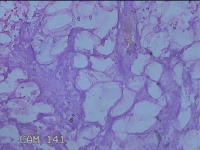

左侧额部结节

性别

男

年龄

29岁

临床诊断

皮脂腺囊肿

一般病史

发现左额部结节1周余。

标本名称

大体所见

灰白粉红色带皮肤样结节1x0.8x0.7cm一个,表面光滑,切开结节呈实性,切面灰白粉红色,质软。